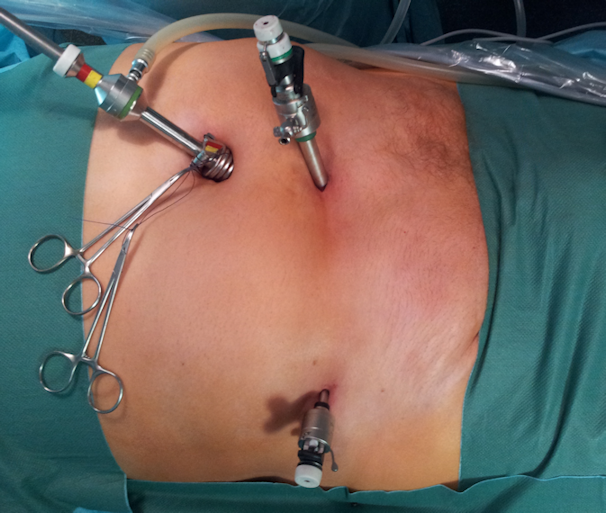

Alle laparoskopischen Verfahren haben gemeinsam, dass sie nur unter Allgemeinnarkose durchgeführt werden können [81]. Eine lokale Anästhesie, wie sie bei den konventionellen Zugangswegen möglich ist, ermöglicht keine ausreichende Relaxation der Bachdecke und ist somit für den laparoskopischen Zugang im Allgemeinen unzureichend. Auch sollten mit diesen Verfahren nach Möglichkeit keine Notfall-Operationen durchgeführt werden, da die laparoskopische Operation einer inkarzerierten Hernie hohe Anforderungen an den Operateur stellt und ein erhöhtes Infektionsrisiko auf Grund der häufigeren Darmverletzung besteht [93], [94]. Somit ist mit einer erhöhten Rate an Komplikationen und möglicherweise Netzinfekten zu rechnen. Letztlich ist dies allerdings eine Einzelfallentscheidung und stark abhängig vom durchführenden Operateur und Zentrum. Generell sollte im Notfall die Technik angewendet werden, die am sichersten beherrscht wird und die das geringste Risiko für den Patienten darstellt. Alle laparoskopischen Zugangswege werden normalerweise mit drei Trokaren durchgeführt (Abbildung 16 [Abb. 16]). Im Bestreben die Operation so wenig invasiv und die Narbenbildung so gering wie möglich zu halten, gibt es aber für die TEP als auch die TAPP schon verschiedene Vorgehensweisen, die mit weniger, zum Teil sogar nur mit einem Trokar, auskommen [95], [96].

Abbildung 16: Aufsicht auf die laparoskopische Operation einer Hernia inguinalis links. Zugang mit drei Trokaren (umbilikal 10 mm, suprapubisch 10 mm und kurz über der Spina iliaca anterior superior der betroffenen Seite 5 mm).